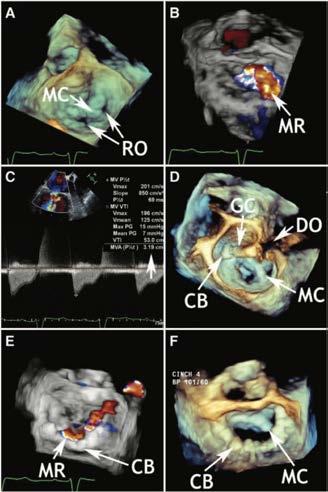

Innovative Medical Devices in Cardiology Shaping the Future of Medicine

A lot of new medical devices to be deployed via percutaneous and other minimal invasive approaches have been introduced during the last two decades. Most important reasons for this ongoing development are complex cardiac conditions as well as increasing age and comorbidities of patients we are confronted with in cardiology.